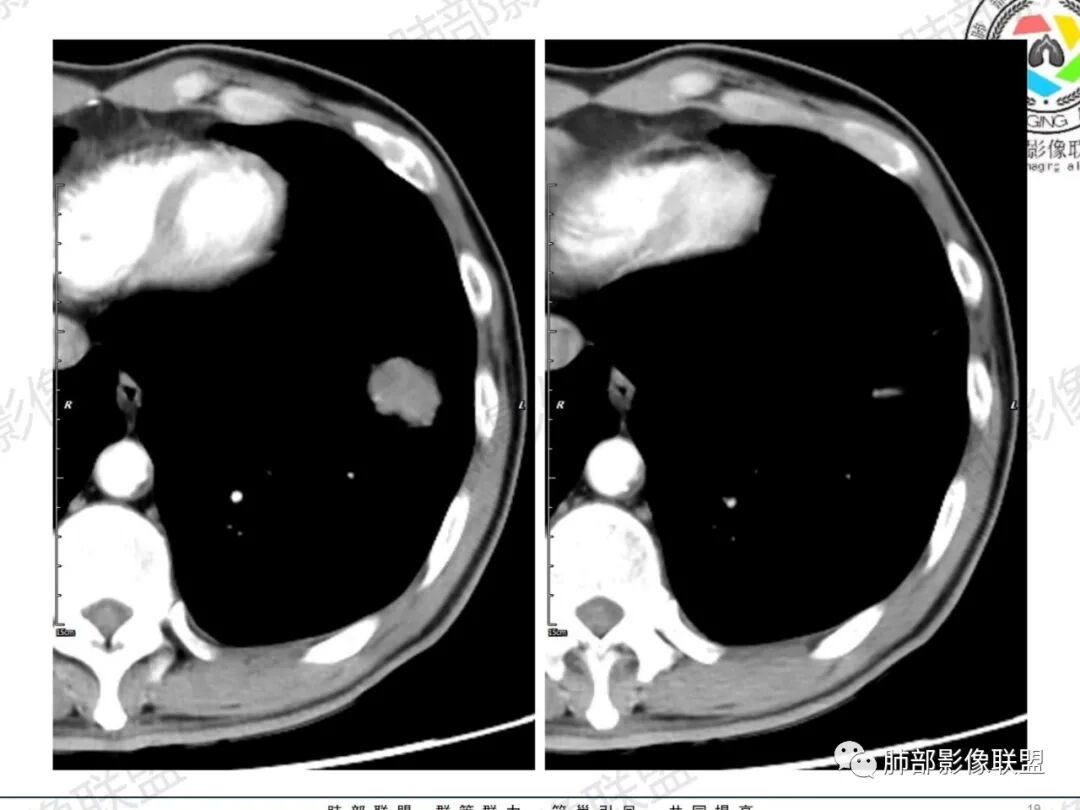

一切∮随缘:左肺下叶不规则肿块,边缘光滑,平直,局部彭隆,分叶,近端支气管堵塞,远端与胸膜相贴,平扫密度尚均匀,增强后不均匀强化,内部可见低密度坏死,胸膜下多发肺气肿,伴双肺散在光滑小结节,实验室肿瘤标志物高,考虑恶性:神经内分泌癌(大细胞),腺癌,鳞癌。

琦遇:恶性没有问题,肺气肿底子、病灶分叶、少许毛刺、叶间胸膜凹陷、部分边缘可见清晰的GGO、胸膜牵拉凹陷、局部胸水、近端支气管截断、部分支气管被推移、占位效应明显、强化特点为不均匀强化、内部有少许沼泽样低强化区,强化部分轻中强化为主、余肺可见转移性结节、左肺上叶似为囊腔型腺癌一枚,肿瘤标志物提示非小、神经内分泌,综合分析考虑大神泌、腺癌、腺鳞癌、鳞癌  同时左肺上叶囊腔型腺癌  肺转移

飞鹰行动:中年人,男性,胸疼入院,左肺下叶占位,张力较高,边界可见分叶,局部可见明显收缩性改变,增强病灶内部有延迟强化表现,考虑恶性病变,大细胞癌伴肺内转移或者囊腔样腺癌伴转移。

傅昌瑜:中老年男性,肺气肿背景,右胸背疼痛1周。CEA、NSE、CYFRA—211升高。左上肺混合磨玻璃结节,内见较多空泡和扩张支气管。左下肺胸膜下肿块,边缘较光滑,深分叶,似有血管进入,与支气管关系不清,内见不均匀强化,见沼泽地样坏死,有胸膜栽赃。另两肺多发圆形小结节。考虑恶性并肺内转移,多原发可能性大,左上肺腺癌,左下肺病理难以判断,小细胞癌?鳞癌?

小锁:中老年男性,肺气肿背景,右胸背疼痛1周。CEA、NSE、CYFRA—211升高。左上肺混合磨玻璃结节,边界清楚,内见较多空泡。左下肺肿块,边缘清楚,深分叶,有血管和支气管进入,胸膜凹陷。另两肺多发圆形小结节。考虑双发原位癌,左上肺腺癌,左下肺大神泌或腺鳞癌可能,肺内转移。

蓝天白云:中年男性,肺气肿背景,左肺下叶肿块,边缘膨隆,有分叶,内有湖泊样坏死,有轻中度强化,局部胸膜栽赃,收缩力不强,周围见肺气肿征象。左肺上叶混合磨玻璃影,边界清楚,考虑都是恶性,左上肺iac,左下肺腺鳞癌,或大细胞肺癌可能。两肺多发结节,考虑转移

LCNEC最常见的影像特征包括:(1)肿块发生部位:周围型肺癌为主,少数发生于肺中央。(2)肿块大小及形态。因肿瘤细胞生长迅速常形成较大肿块,因此其体积一般较大,直径常在3~10cm范围内,病灶常为不规则形软组织肿块。(3)肿块边界。多数学者报道大多数肿块边界清晰,边缘呈分叶状,毛刺征及“胸膜凹陷征”少见,认为与该病对周围组织浸润较轻及较少产生纤维瘢痕组织牵拉有关联。(4)肿块密度、强化特点及代谢情况。据文献报道,该类肿瘤因体积较大CT上常见软组织肿块,且多数密度不均匀,内见囊变坏死区,增强后呈轻或中度不均匀强化(可见强化者占75.7%),认为其强化特点与其内部肉眼可见坏死灶和肿瘤较大直径有关。(5)伴随症状及远处转移。该病恶性程度高,侵袭性强,常侵犯邻近结构,如胸膜、心包、邻近骨质或纵隔内组织等,易出现纵隔淋巴结转移,部分发生肺内及远处转移,少数早期可出现广泛远处转移。